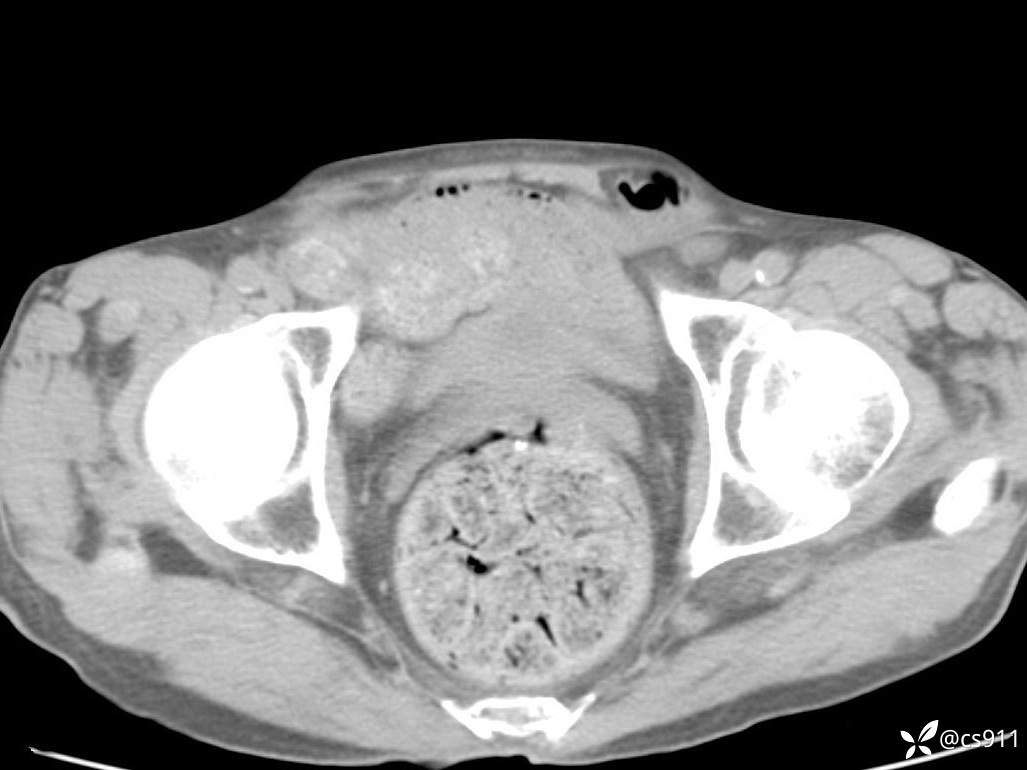

急腹症之急诊CT,原因?答案公布

男,77岁,腹痛、腹胀伴恶心呕吐1天。呕吐胃内容物,非喷射性呕吐,有咖啡色样胃内容物,诉有胃穿孔病史。查体:全腹平,下腹部压痛,全腹无反跳痛,叩诊呈浊音,移动性浊音阴性,肠鸣音减弱,1-2次/分。肛检:直肠未扪及明显肿物,可触及大量粪块。

T 36.6℃ P 80次/分 R 26次/分 BP 100/60mmHg

白细胞(WBC) H 14.55 10e9/L 4-10

红细胞(RBC) 4.58 10e12/L 4.3-5.8

中性粒细胞百分率(NEUT%) H 85.7 % 40-75

血淀粉酶(AMY) HH 1859 U/L 35-135

癌胚抗原(CEA) H 27.44 ng/ml 0-5

呕吐物 潜血试验 * 阳性 阴性

患者轮椅入室检查神志清楚, 能配合摆位和呼吸